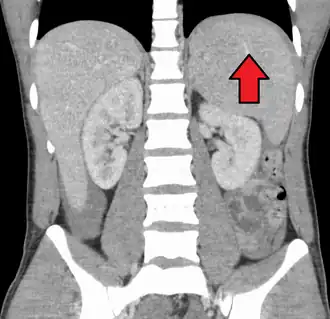

| Complications | Swelling of the liver or spleen[3] |

Infectious mononucleosis (IM, mono), also known as glandular fever, is an infection usually caused by the Epstein–Barr virus (EBV).[2][3] Most people are infected by the virus as children, when the disease produces few or no symptoms.[2] In young adults, the disease often results in fever, sore throat, enlarged lymph nodes in the neck, and fatigue.[2] Most people recover in two to four weeks; however, feeling tired may last for months.[2] The liver or spleen may also become swollen,[3] and in less than one percent of cases splenic rupture may occur.[6]

Spleen enlargement is common in the second and third weeks, although this may not be apparent on physical examination. Rarely, the spleen may rupture.[27] There may also be some enlargement of the liver.[25] Jaundice occurs only occasionally.[16][28]

Physical examination

The presence of an enlarged spleen, and swollen posterior cervical, axillary, and inguinal lymph nodes are the most useful to suspect a diagnosis of infectious mononucleosis. On the other hand, the absence of swollen cervical lymph nodes and fatigue is the most useful to dismiss the idea of infectious mononucleosis as the correct diagnosis. The insensitivity of the physical examination in detecting an enlarged spleen means it should not be used as evidence against infectious mononucleosis.[25] A physical examination may also show petechiae in the palate.[25]

Infectious mononucleosis is generally self-limiting, so only symptomatic or supportive treatments are used.[50] The need for rest and return to usual activities after the acute phase of the infection may reasonably be based on the person's general energy levels.[25] Nevertheless, in an effort to decrease the risk of splenic rupture, experts advise avoidance of contact sports and other heavy physical activity, especially when involving increased abdominal pressure or the Valsalva maneuver (as in rowing or weight training), for at least the first 3–4 weeks of illness or until enlargement of the spleen has resolved, as determined by a treating physician.[25][51]

Observation

Splenomegaly is a common symptom of infectious mononucleosis, and healthcare providers may consider using abdominal ultrasonography to get insight into the enlargement of a person's spleen.[61] However, because spleen size varies greatly, ultrasonography is not a valid technique for assessing spleen enlargement. It should not be used in typical circumstances or to make routine decisions about fitness for playing sports.[61]